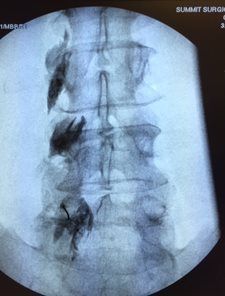

- Epidural injections with x-ray guidance

- Facet nerve blocks with x-ray guidance

- Spine facet joint injections